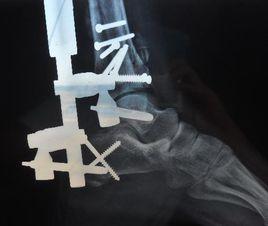

(2)20 世紀 80 年代以後逐步完善了對關節內骨折的治療認識,隨著內固定技術和器材的逐步改進,關節內骨折的治療方法逐步完善,結果大有提高,不僅使新鮮骨折獲得解剖復位,對陳舊骨折,也能切開復位獲得解剖復位,堅固內固定的早期活動,使創傷性關節炎的發生率大大降低,關節活動功能獲得最大限度恢復。

6、關節內骨折的治療原則:1987年Schatzker闡明了關節內骨折的治療原則,強調解剖復位、堅強內固定和早期功能訓練的重要性,指出主要關節面的整合是關節內骨折復位的關鍵之一,至今該項原則仍是關節內骨折的處理原則。關節內骨折的治療原則:堅強內固定;避免術後外固定;乾骺端的骨缺損應予以指骨;糾正乾骺端力線。

較小的骨折可以採用縫合法固定、克氏針固定,較大的骨折塊可採用松質骨螺釘固定。近幾年用可吸收高分子材料研製的螺釘已較多地用於關節內骨折內固定,具有固定可靠、可降解、不需再手術取出、材料降解產物為水和二氧化碳、可被機體排出等優點。但降解產物為酸性,在一些較敏感的病人可能產生無菌性炎症反應,在臨床套用時,應注意觀察,並及時處理 。